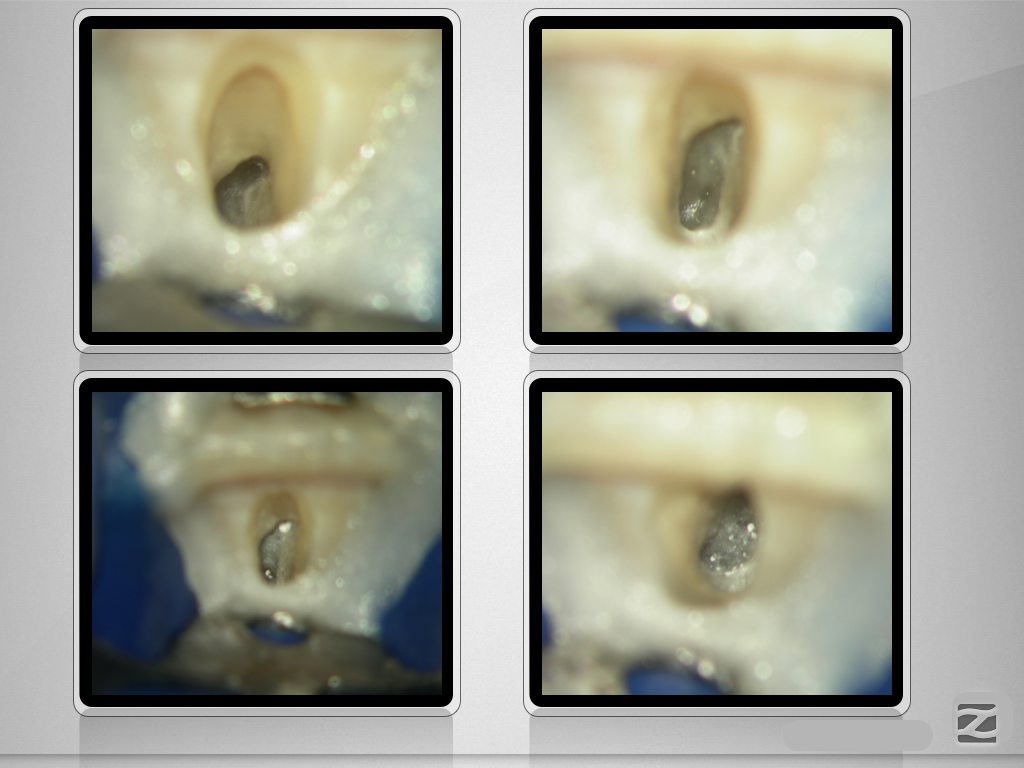

Folgen eines Milchzahntraumas (2)